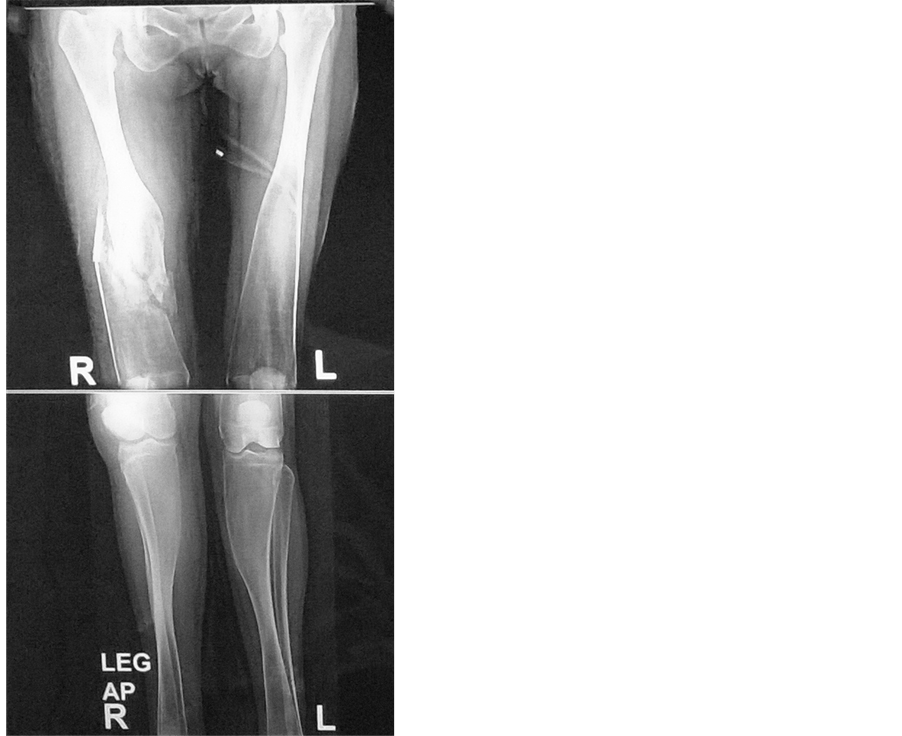

Fracture Femur in a Case of Pyle’s Disease A Case Report Pyle Disease Pyle disease is a rare bone disorder characterized by long bones with wide metaphyses, thin cortical bone, and bone fragility leading to fractures. Pyle disease is a bone disorder characterized by knock knees (genu valgum), relative constriction of the diaphysis or shaft of the bone and flaring. A rare bone dysplasia characterized by long bones with wide and expanded metaphyses,. Pyle Disease.

Fracture Femur in a Case of Pyle’s Disease A Case Report Pyle Disease Its hallmark feature is an abnormality of the long bones in the arms and legs in which the ends. Metaphyseal dysplasia, also known as pyle disease, is a rare bone disorder characterized by thin outer shafts of long bones, making them. A rare bone dysplasia characterized by long bones with wide and expanded metaphyses, thin cortical bone and bone fragility.. Pyle Disease.

Fracture Femur in a Case of Pyle’s Disease A Case Report Pyle Disease Metaphyseal dysplasia, also known as pyle disease, is a rare bone disorder characterized by thin outer shafts of long bones, making them. Its hallmark feature is an abnormality of the long bones in the arms and legs in which the ends. Pyle disease is a bone disorder characterized by knock knees (genu valgum), relative constriction of the diaphysis or shaft. Pyle Disease.